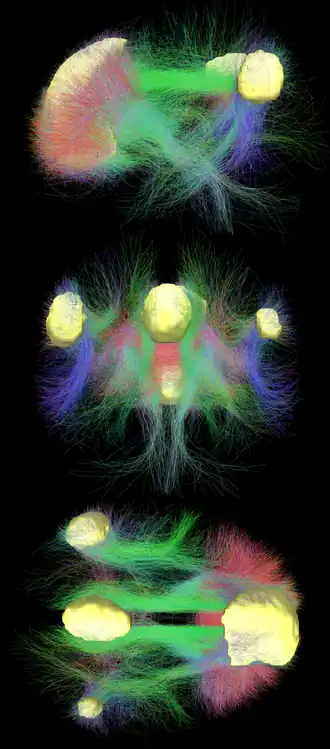

Default mode network connectivity. This image shows main regions of the default mode network (yellow) and connectivity between the regions color-coded by structural traversing direction (xyz → rgb).[1][2]

Diffusion MRI imaging shows white matter tracts connecting different areas of the DMN together.[22] The structural connections found from diffusion MRI imaging and the functional correlations from resting state fMRI show the highest level of overlap and agreement within the DMN areas.[1] This provides evidence that neurons in the DMN regions are linked to each other through large tracts of axons and this causes activity in these areas to be correlated with one another. From the point of view of effective connectivity, many studies have attempted to shed some light using dynamic causal modeling, with inconsistent results. However, directionality from the medial prefrontal cortex towards the posterior cingulate gyrus seems confirmed in multiple studies, and the inconsistent results appear to be related to small sample size analysis.[28]